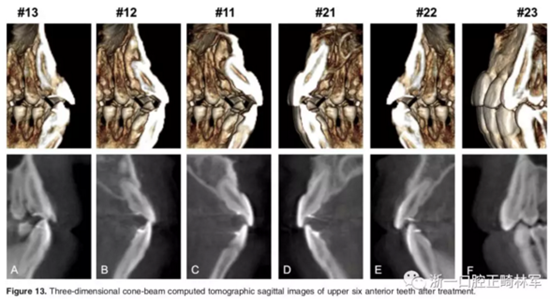

影像學:頭顱側位片示:矢狀向和垂直向骨骼發(fā)生變化(ANB角,3°;SN-MP,51°);上頜切牙略前傾(U1-SN,106°),與下頜切牙一致(IMPA,75°);病人的面部輪廓得以保持。全景片示:由于牙齒萌出,上前牙區(qū)垂直向牙槽骨水平增加;雖然前牙牙根較彎曲,但其平行度仍可,且無明顯的牙根吸收。CBCT示:前牙唇側骨質(zhì)連續(xù)性改善,牙根唇側支持組織變好,牙槽骨高度、厚度均有增加,但轉(zhuǎn)矩的改變一定程度上導致了局部應力的增大。